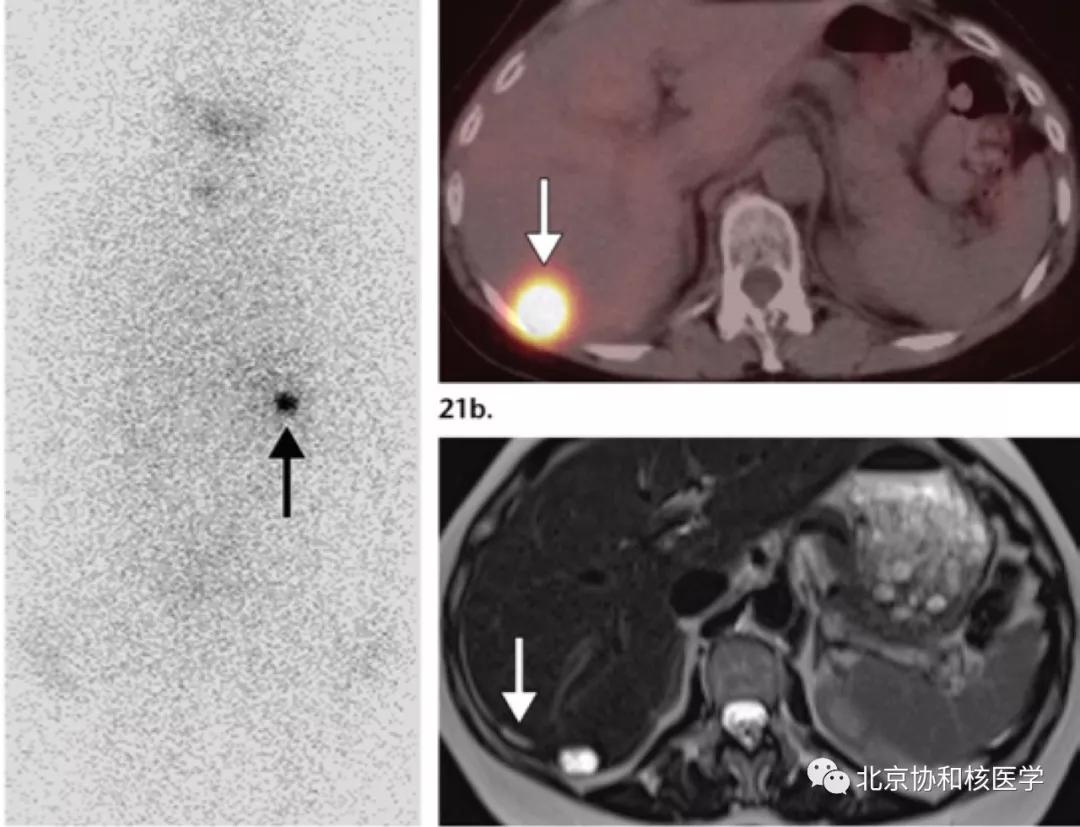

肝周或肝被膜下囊肿所致碘摄取:

单纯肾囊肿的碘摄取,可能由于囊液与集合系统的交通或碘通过囊肿上皮细胞分泌入囊内停留形成: